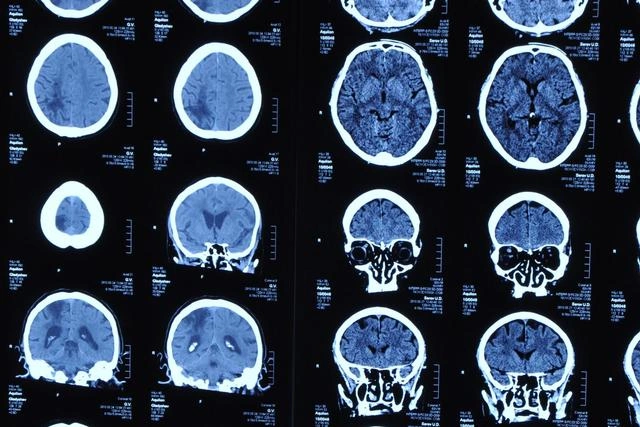

Во время выполнения напряженных задач мозг проявляют особую активность. Именно по ней финские ученые и попытались отследить людей с признаками выгорания, связанного с работой (утомление, снижение концентрации, ослабление памяти, цинизм, снижение эффективности труда), пишет Меддейли.

К примеру, у них ослабевает ответ в задней части мозга. Зато повышается активность во фронтальной зоне. По статистике, выгорание довольно распространено. К примеру, в Финляндии это касается каждого четвертого, а в США – 64% работников. Выгорание грозит целым набором неприятных последствий и для компании, и для работника.

Используя электроэнцефалограмму, ученые проанализировали нейронный ответ 41 добровольца, пока те выполняли задания на слух, внимание, качество памяти. Задания требовали быстрого принятия решения и дифференциации разных типов заданий. Оказалось, у людей с выгоранием наблюдается уникальная активность мозга. Например, они не реагировали на раздражающие звуки.